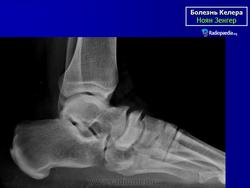

Здравствуйте Валентин Львович!

подскажите, пожалуйста, можно ли эти снимки трактовать как представленную выше б-нь Келлера?

(не особо  беспокоит. Со слов: "болит немного только после долгой прогулки")

Келера, в данном случае ни при чём.

Продольное плоскостопие 3 ст.

и ладьевидная и таранная нормальные?

Конечно нет